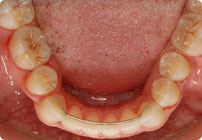

Retenedores: Inferior Fijo

Galería

Femenino

Antes

Despues

Caso: 19 años

Adulto: Clase III

Mordida Abierta Anterior

Mordida Cruzada Anterior y Posterior

Endo necesitado para #19

Extract U5’s, LR4, LL6

6 alambres superiores

5 alambres inferiores

Elásticos Clase III 2oz. TP Verde

Retenedores: Interior Fijo de TMA y Hawley en superior

Tiempo de tratamiento: 21 Visitas